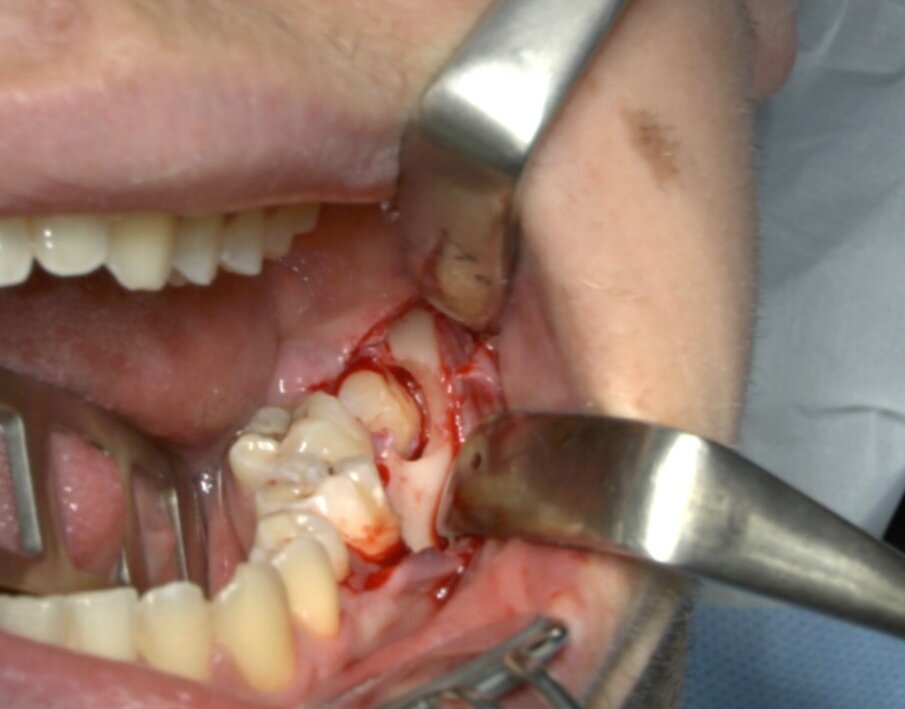

Protocollo standard

Ai pazienti viene prescritta una profilassi antibiotca con 2 gr di amoxicillina 1 h prima dell’intervento, si esegue quindi un anestesia di tipo tronculare con lidocaina senza vasocostrittore, poi infiltrazione di tipo plessica con adrenalina in corrispondenza del nervo buccinatore. Si scolpisce quindi un lembo a tutto spessore di tipo triangolare con incisione orizzontale alla base delle papille tra sesto e settimo ed incisione di scarico distale con andamento vestibolare (Figg. 1-4). Si procede con l’osteotomia che può essere eseguita con strumenti rotanti montati su manipolo retto oppure con terminale piezoelettrico con gli inserti dedicati. Qualora sia necessario si effettua l’odontotomia e la separazione radicolare con frese al carburo di tungsteno montate su turbina, quindi si esegue la lussazione e l’avulsione dell’elemento dentario. Si procede alla revisione della cavità alveolare con abbondante lavaggio con soluzione fisiologica, riempimento con collagene e sutura a punti staccati in seta 4/0. Il paziente viene dimesso con terapia analgesica ed antibiotica di supporto (Figg. 5-15).

Fig. 5_Ostectomia con terminale piezoelettrico.

Fig. 6_Terminale piezoelettrico in azione.